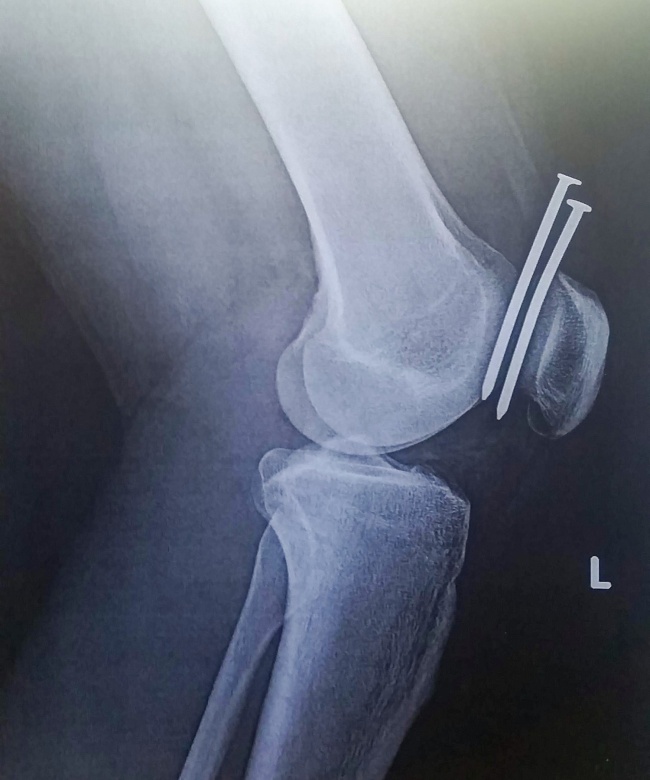

16. Les espaces dans le corps humain sont salvateurs

Illustration de l'article : Ces 20 personnes vous racontent leur histoire le jour où ils ont frôlé le drame !

© ILLMATIC1994/imgur

C’est avec une agrafeuse-cloueuse que cet homme s’est planté ces deux clous de calibre 16 dans le genou. La radio a montré qu’ils s’étaient logés dans l’espace entre son fémur et sa rotule !